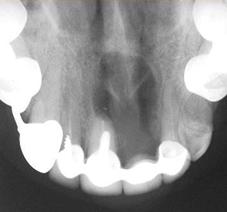

1) Внутриротовая контактная рентгенограмма.

Позволяет оценить степень резорбции костной ткани альвеолярного отростка (при снижении высоты на 1/3 и ниже проведение зубосохраняющей операции нецелесообразно). Состояние канала корня зуба, степень и качество его пломбирования. Наличие отломков инструментов в канале, наличие перфораций. Взаимоотношение кисты с корнями соседних зубов. Взаимоотношение корней соседних зубов с кистозной полостью может варьировать. Если корни вдаются в полость кисты, на рентгенограмме периодонтальная щель отсутствует вследствие рассасывания замыкательной пластинки лунок этих зубов. Если же периодонтальная щель определяется, то такие зубы только проецируются на область кисты, а на самом деле корни их располагаются в одной из стенок челюсти.

Рентгенологическая картина.

При рентгенологическом исследовании, поимо выявления околокорневой кисты в виде просветления округлой или овальной формы, окружающей корень зуба, важно оценить состояние самого причинного зуба, в частности степень разрушения связочного аппарата (периодонта), состояние канала корня, которое может характеризоваться следующими признаками: